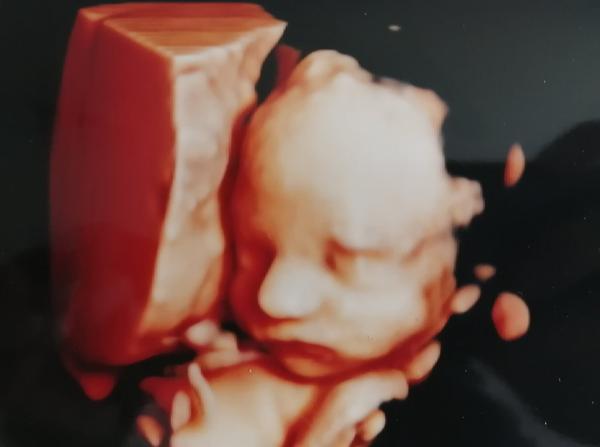

Ve 26-28.tt s obouma synama jsem byla cca v gennetu ☺️A za me parada ..u prvnihu tehu me diky tomu konecne nekdo rekl co čekame 😂

@markytkynka jooo ten druhej syn teda trochu stavkoval ale nakonec se umoudril☺️ A ta cena je vsude cca stejna ☺️